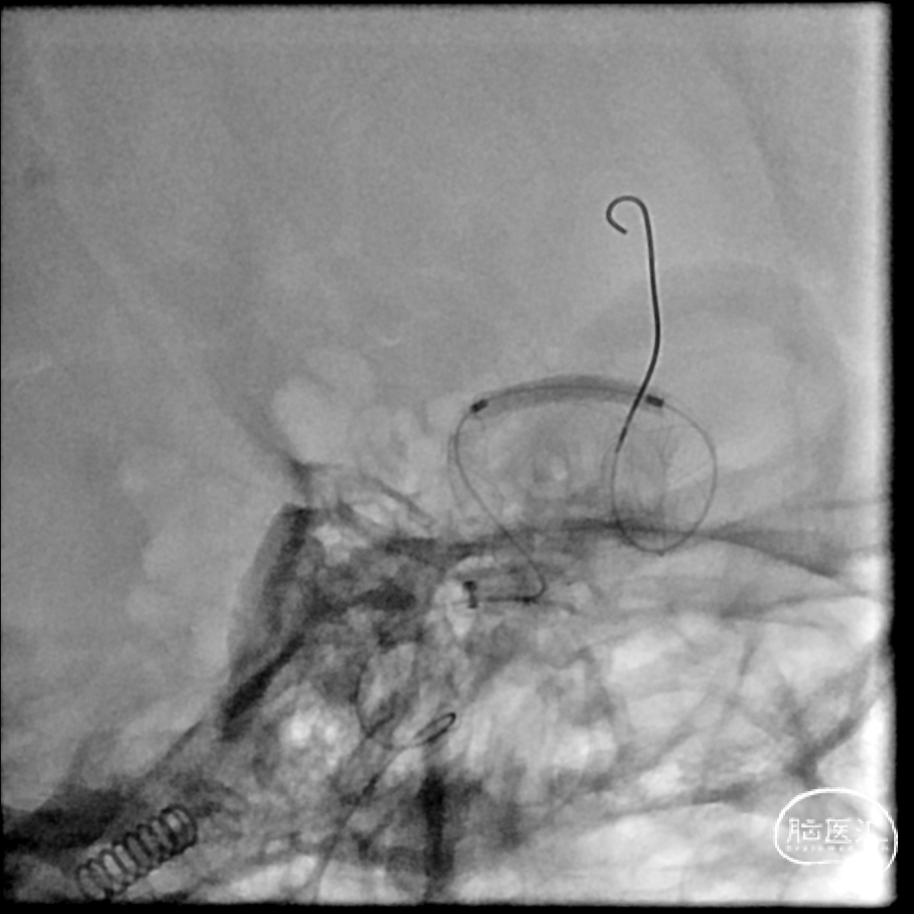

支架打开不良

支架重新打开良好

再次交换3m Floppy

Maverick 2mm/15mm,6atm

2、本案例大脑中动脉起始部极重度狭窄是FD治疗的难点,支架导管通过困难、支架打开困难。

2、治疗策略的选择:鉴于该例夹层动脉瘤受累血管段较长且合并近端狭窄,在治疗策略上,可以选择颞浅动脉双干搭桥或高流量搭桥联合夹层动脉瘤夹闭或孤立的手术方式,但缺血性事件风险无法完全避免,特别是当豆纹动脉受累时。单支架辅助弹簧圈栓塞技术治疗夹层动脉瘤存在较高的远期复发率,对狭窄段的径向支撑力可能也欠缺;多支架套叠在预防夹层动脉瘤复发有更好的结果,但该例夹层动脉瘤的近端狭窄段和迂曲血管段都增加了多支架操作的难度;选择合适的血流导向装置植入可以获得即刻的重建血流并对狭窄段血管提供持续扩张能力,是更有希望的可行方案。在本例患者中,我们先对近端狭窄血管段进行预扩张,再对血流导向装置释放后的狭窄段进行支架内扩张,得到了较好的结果。

4、展望:血流导向装置治疗未破裂的大脑中动脉大型夹层动脉瘤是可行的和安全的,但在弯曲段及合并狭窄的血管条件下,支架打开困难、贴壁不良和扭结是面临的主要技术难题,结合球囊扩张可以辅助支架更好的释放。术前术后多模态、多维度的评估以及密切的随访是必要的。